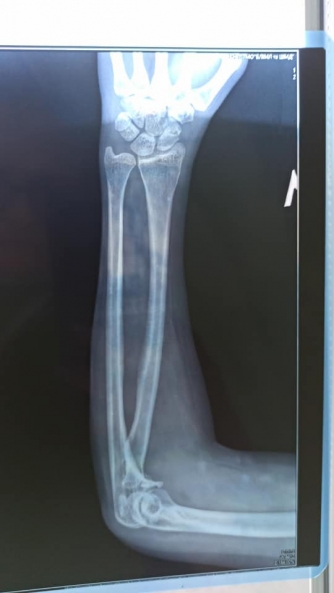

К посту-просьбе прилагается рентген снимок и заключение врача, в котором указано, что у велосипедистки "перелом венечного отростка левой локтевой кости со смещением и оскольчатый перелом головки левой лучевой кости".